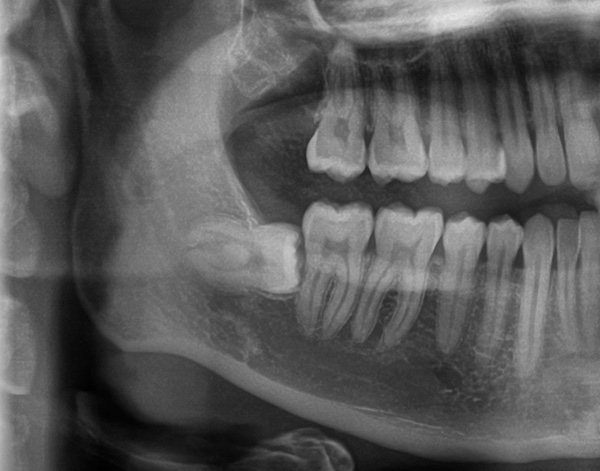

Quando un dente che è stato completamente distrutto dalla carie non è stato trattato per molti anni, continua a "marcire" gradualmente e si verificano processi infiammatori sulle sue radici. Il corpo per qualche tempo limita l'insorgenza dell'infezione e ne limita la diffusione, circondando la capsula a guscio: granuloma o cisti.

La foto sotto mostra il dente estratto con le cisti sulle radici: